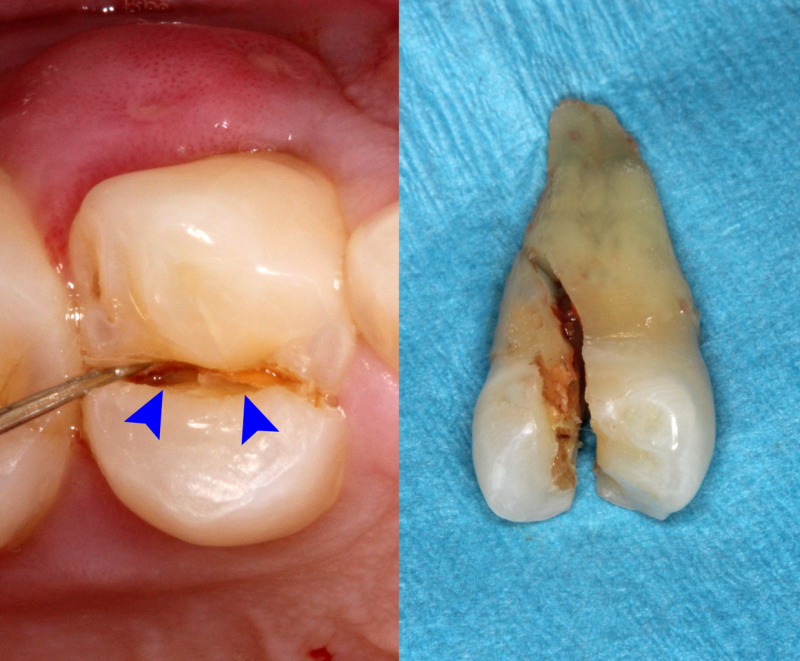

Cracked tooth is basically an incomplete fracture of the dentine in a tooth that involves dentine and occasionally extends into the pulp.The term cracked tooth syndrome was first introduced by Cameron in the year 1964.It is also termed as cracked cusp syndrome, or split tooth syndrome.Cracked tooth syndrome could be considered a type of dental trauma and also one of the causes of dental pain.

If the crack extends, a piece of the tooth may break off. There’s an increased risk of developing an infection in gums around the fractured tooth. You may notice a bump on the gum.